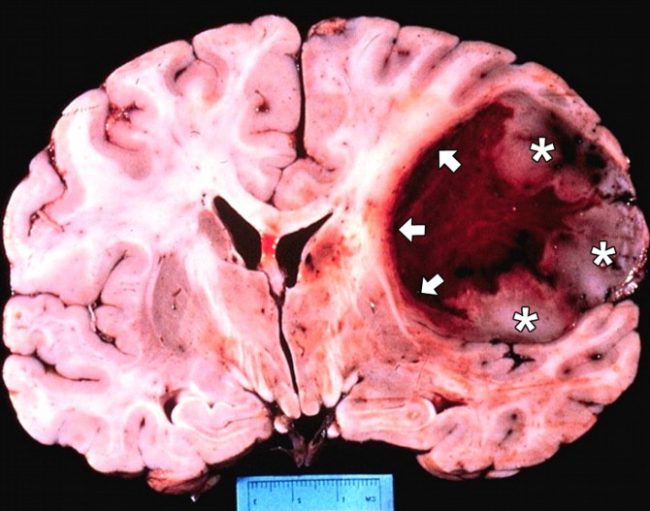

Фото рака головного мозга:

Более опасными являются опухоли второго типа, так как злокачественные клетки с нарушенным генетическим кодом не отмирают, как обычные структуры, а быстро делятся, поражая большие площади. Злокачественные опухоли дополнительно подразделяются на первичные и вторичные. Первичные являются продуктом сбоев в работе нервных клеток (глиомы), а вторичные появляются в результате разноса по организму метастазов.